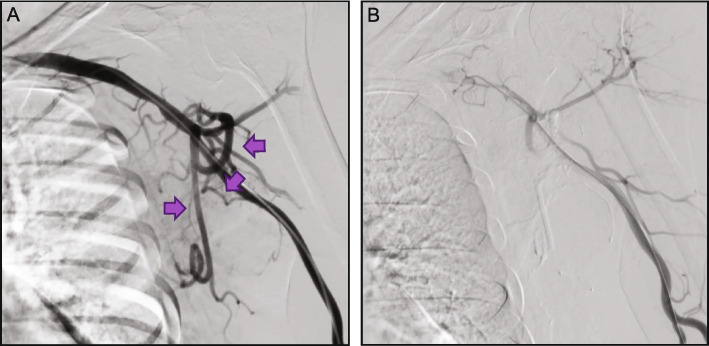

Background: Obsidio Conformable Embolic (Obsidio) is a ready-made hydrogel with unique shear-thinning properties, used for occlusion of blood flow to control bleeding or hemorrhage in the peripheral vasculature and embolization of hypervascular tumors. While pre-clinical and clinical data have demonstrated successful embolizations using Obsidio, clinical experience overall is still limited, prompting a multi-institutional field assessment survey to collect additional data on the clinical utility and procedural details from a variety of Obsidio users. The field survey collected data from 131 embolization procedures performed using Obsidio between May and November 2023 at 27 institutions within the United States. Data collection included embolization site, vessel size, any adjunctive embolics used. The primary objective of the survey was to evaluate technical success, defined as complete embolization of the target vasculature immediately following the index procedure, as confirmed by angiography.

Results: Of the 131 embolization procedures performed, 69% (n = 90) were for hemorrhage control, 15% (n = 19) were for hypervascular tumors, and 17% (n = 22) were for other indications. Embolization of the gastroduodenal artery was the most common indication (n = 19/131; 15%). A single syringe (1 mL) or less of Obsidio was used for most cases (93%). In 33/131 cases (25%), Obsidio was combined with other embolization devices including coils (n = 25; 19%), particle-based embolics (n = 6; 4.6%), or plugs (n = 2; 1.5%). Technical success was achieved in 100% of Obsidio embolization cases (131/131 procedures).

Conclusion: Initial clinical experience demonstrated successful embolization of end-organ bleeds and hypervascular tumors utilizing Obsidio, thus making it an effective embolic agent alone or in conjunction with other embolic devices.